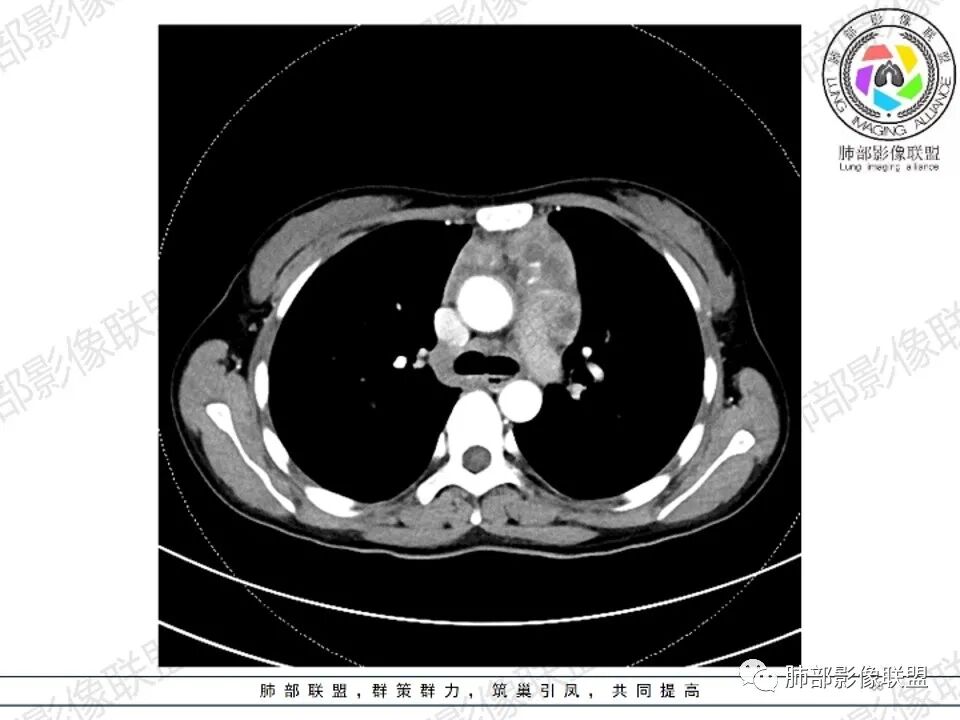

纵隔多发结节堆积 塑型生长  质软 边界不清 强化不均  双侧腋窝淋巴结肿大

年轻女性,贫血,CT示前纵隔团片状软组织占位,多结节堆积感,塑形生长,边界欠清,包绕大血管及心包,增强明显不均匀强化,内见血管漂浮。纵隔4R,5,7区及双侧腋窝多发肿大淋巴结,综合考虑为淋巴瘤可能

前纵隔不规则肿块,多结节融合,边界欠清,延周围脂肪间隙生长,包绕主动脉及肺动脉血管,平扫密度欠均匀,增强扫描可见多发低密度坏死,并可见一条血管穿行,腋窝多发大小不等淋巴结肿大,年轻女性,考虑恶性:淋巴瘤,胸腺癌,肉瘤,浆细胞瘤

女,27,间断头晕、乏力3年,左眼视物模糊2月。贫血。胸部CT:前纵隔不规则肿块,多结节融合,边界不清,沿主动脉及肺动脉间隙生长,平扫密度欠均匀,增强扫描可见多发低密度坏死,纵隔血管供血穿行,腋窝多发大小不等淋巴结肿大。考虑恶性病变,胸腺癌?肉瘤?淋巴瘤?鉴别胸腺瘤、结节病等。

前纵隔和双侧腋窝多发的淋巴结肿大,前纵隔为甚,融合呈中等强化,部分坏死呈低密度,包埋肺动脉主干和左心缘,融合斑块状,内见血管飘浮特点,前纵隔脂肪间隙混浊,首选淋巴瘤!

2.影像显示前纵隔不规则块状影,依势贴附心脏大血管旁,密度不均,边界不甚清楚,有结节融合感。

3.病灶轻度不均匀强化,可见血管穿行,散在液性低密度区。

4.双侧腋窝区见增大淋巴结,边界清楚。

1.年轻女性,前纵隔不规则块状影,密度不均,边界不甚清楚,有结节融合感,轻度不均匀强化,可见血管穿行,最常见最符合的无疑是淋巴瘤!

3、影像学表现:显著肿大强化的淋巴结,常局限性分布;当患者无或仅轻微症状,纵隔内和腹膜后出现单个慢性巨大肿块,CT平扫示肿块边缘清楚,实质密度均匀,尤其是肿块呈显著强化和邻近大血管一致时,提示本病的可能。即使实质密度不均匀,中心液化坏死,但实质部分呈显著强化,与邻近大血管相似时,在鉴别诊断中仍然要考虑到本病的可能。